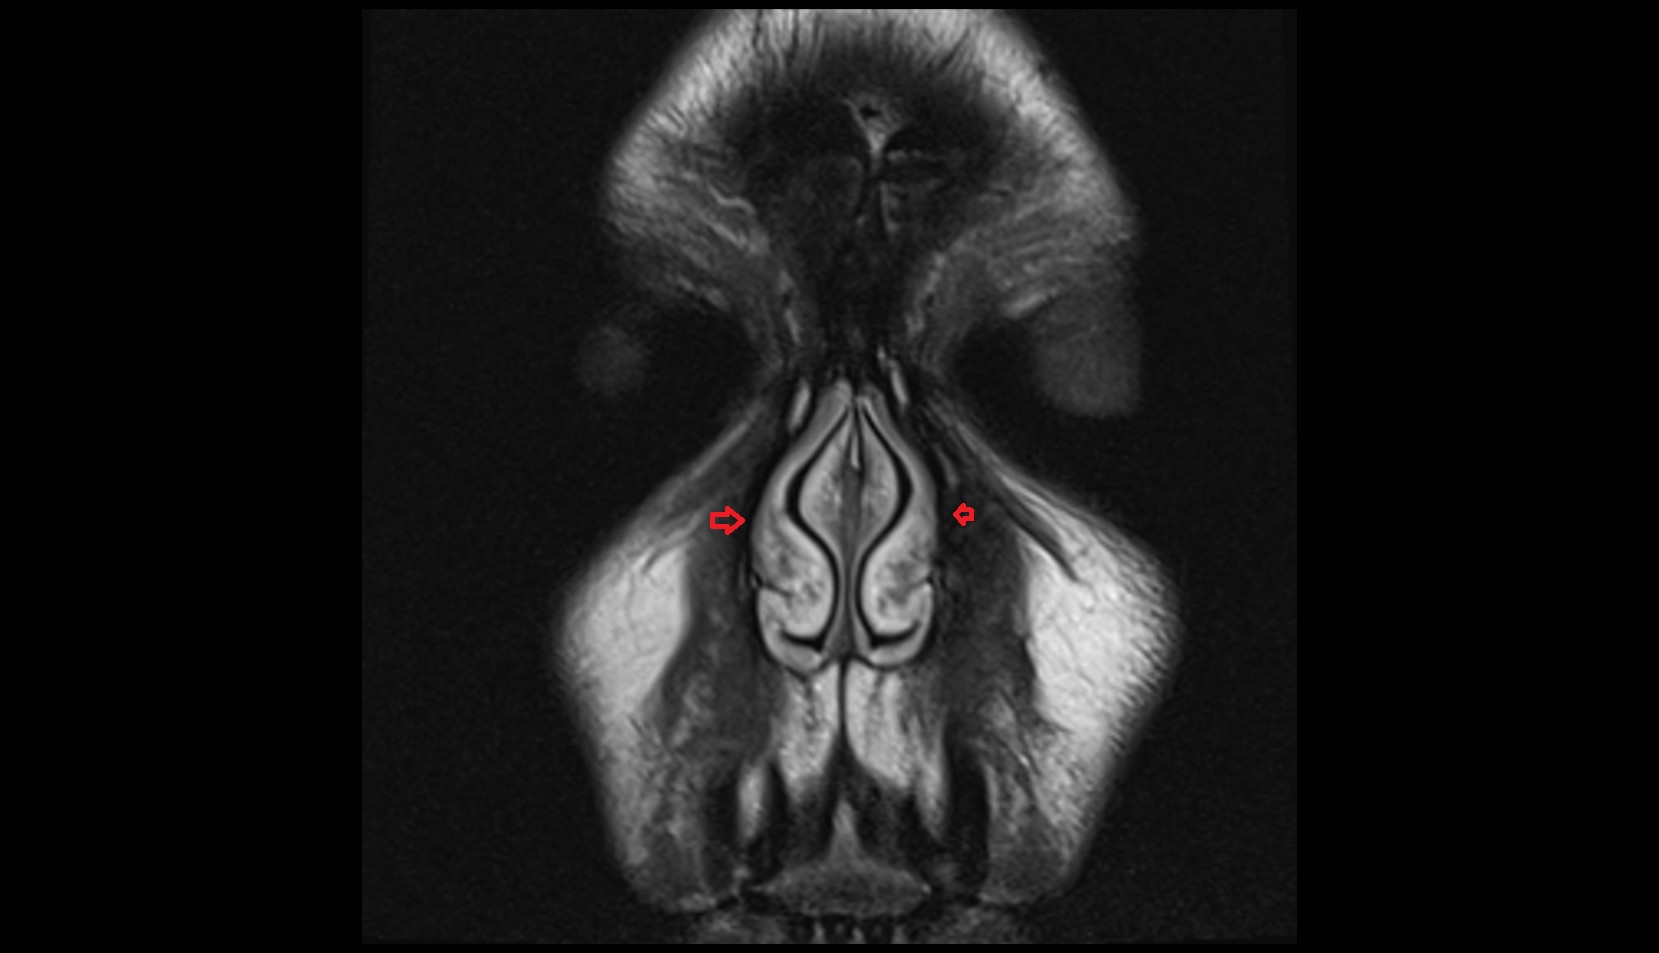

- Body of hippocampus

- Head of hippocampus

- Tail of hippocampus

- Hippocampus